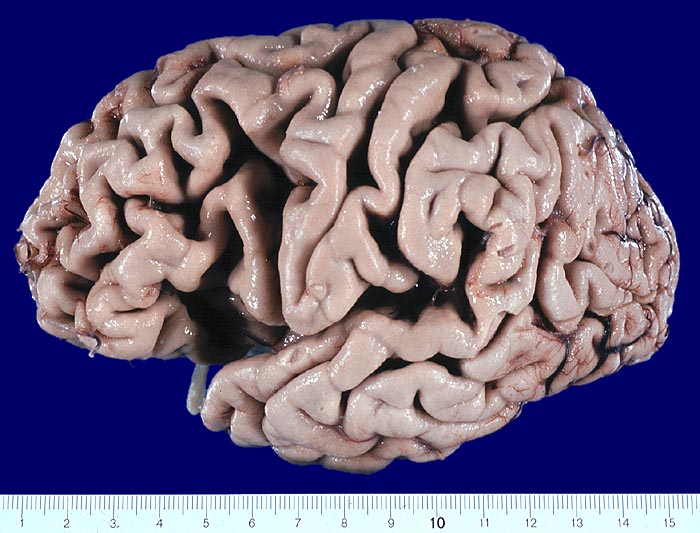

Gehirne von Alzheimer Patienten sind makroskopisch durch eine kortikale Atrophie (vor allem temporo-parietal) charakterisiert. Weiter findet sich meist eine deutliche Atrophie von Hippocampi und Mandelkernen. Diese geht einher mit einem Hydrocephalus internus (e vacuo), wobei vor allem die Temporalhörner der Seitenventrikel betroffen sind.

Makroskopie

Befund

Pathologischer Befund

Normalbefund